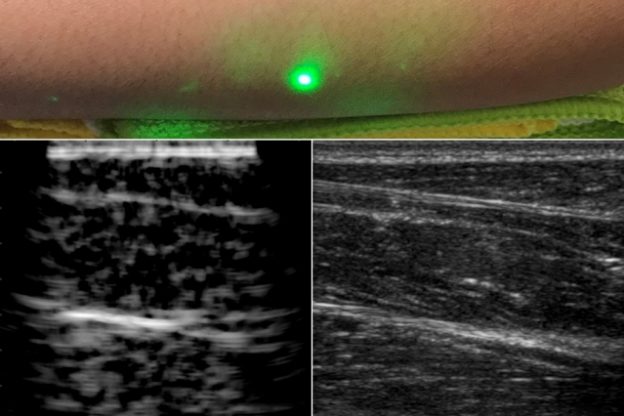

在對數名志願者前臂掃描後,研究人員獲得了第一張完全非接觸式雷射超音波人體影像,從影像中可以看出,雷射超音波可以區分微妙的特徵,脂肪、肌肉和組織的邊界清晰可見,完全可以與需接觸的商業超音波探頭產生的影像相媲美,而且掃描過程還是與志願者保持半公尺距離下完成的。

(首圖來源:MIT